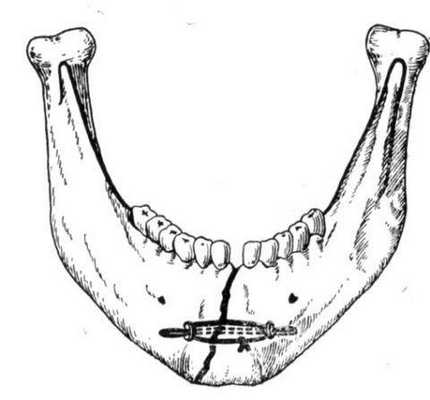

Костный шов

Показанием к этому методу лечения является свежий перелом нижней челюсти скуловой кости с незначительным смещением кости. Противопоказаниями служат: воспалительный процесс в патологическом участке, инфекционное и гнойное поражение кости.

Инструкция по наложению костного шва требует использования проволоки из нержавеющей стали, титана или капроновую нить. В ходе операции специалист рассекает кожный покров и фиксирует костные фрагменты посредством проволочной лигатуры.

Преимущества методики заключаются в сохранении функции жевания и удовлетворительного уровня гигиены ротовой полости.

Данный вариант остеосинтеза показан только при переломе тела нижней челюсти.

Методика радикального вмешательства выполняется в таком порядке:

- хирургическое обнажение костных фрагментов;

- на передней части костной поверхности специалист высверливает специальный желоб;

- пакование пластмассовой массы в костную выямку;

- удаление излишек пластмассы ортопедической фрезой;

- зашивание раны.